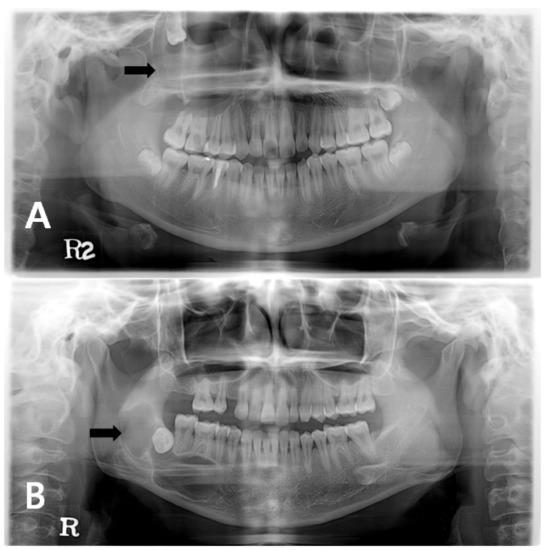

Simple bone cysts (SBC) are pseudocysts occurring less commonly in the maxillofacial region. The uncertain and unclear etiopathogenesis led to numerous synonyms to refer this particular cyst. These cysts are devoid of an epithelial lining and are usually empty or contain blood or [...] Read more.

Simple bone cysts (SBC) are pseudocysts occurring less commonly in the maxillofacial region. The uncertain and unclear etiopathogenesis led to numerous synonyms to refer this particular cyst. These cysts are devoid of an epithelial lining and are usually empty or contain blood or straw-colored fluid. In jaws initially it mimics a periapical cyst and later can lead to cortical bone expansion warranting for radical approach, which is seldom required. SBC is predominantly diagnosed in first two decades of life. Here we report a case of solitary bone cyst mimicking a periapical cyst of a mandibular molar in a 37-year-old patient. Full article